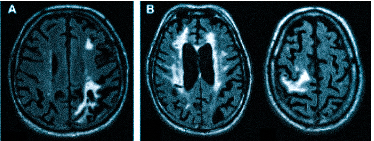

Множественные ишемические очаги при сосудистой деменции на МРТ: отсутствие памяти на недавние события и неадекватное поведение не являются признаками старости, своевременная диагностика деменции и патогенетическая терапия помогут замедлить прогрессирование болезни

МРТ — обследование, которое проводят не только при головной боли. Магнитно-резонансная томография поможет установить причины следующих жалоб: